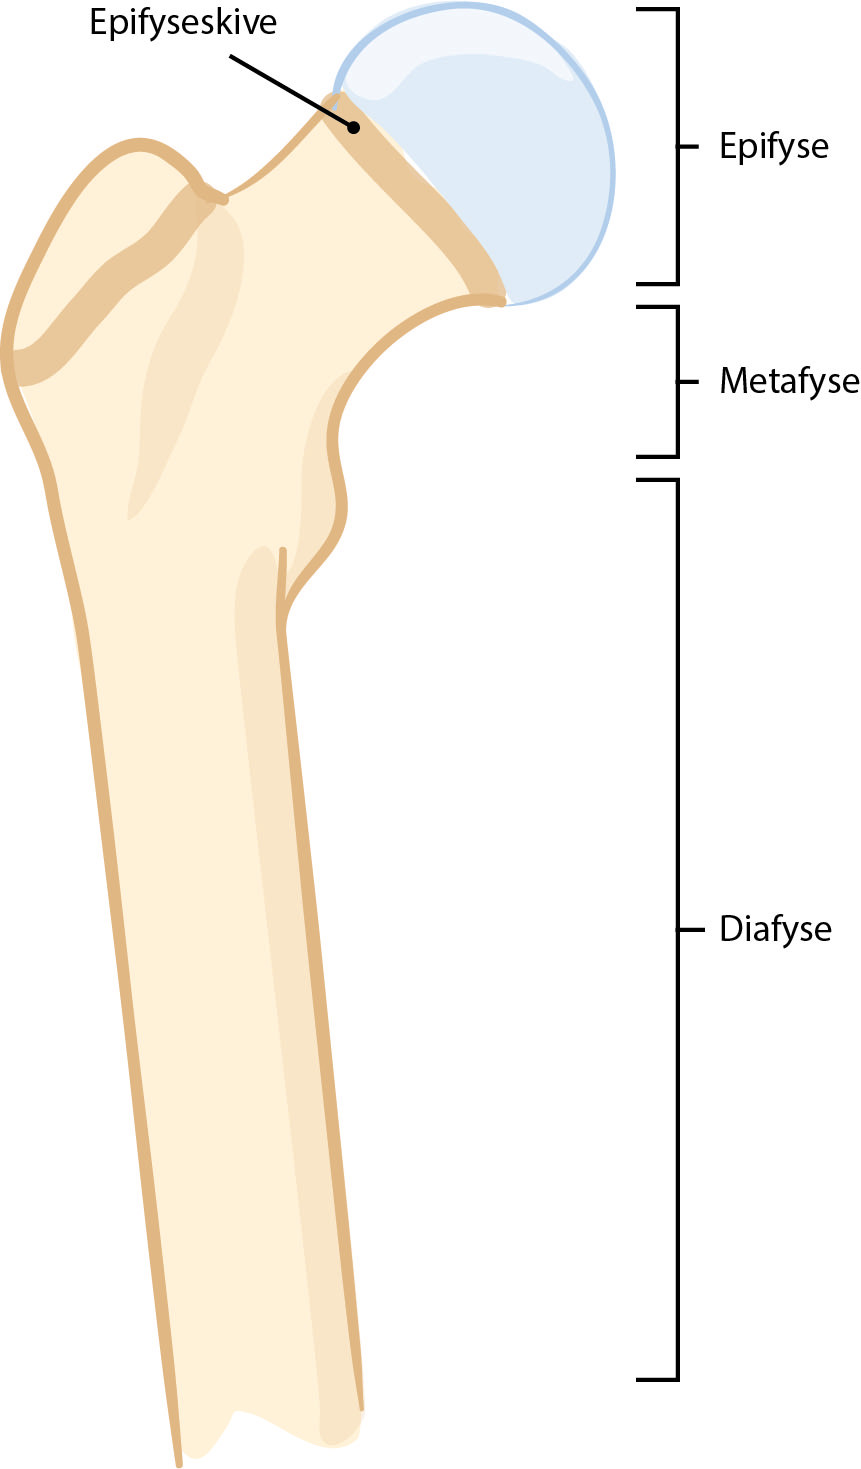

Ved epifysiolysis capitis femoris, epifysiolyse av lårbenshodet, skjer det en glidning i vekstskiven (epifyseskiven) mellom lårbenshodet (epifysen) og lårhalsen (metafysen) øverst i lårbenet (figur 1, figur 2). Gjennomsnittsalderen ved diagnose er 12 år for jenter og 13 år for gutter. Tilstanden forekommer utelukkende så lenge epifyseskiven er åpen, og meget sjeldent ved alder under 9 år og over 16 år. Om lag 25 % får glidning i begge hoftene.